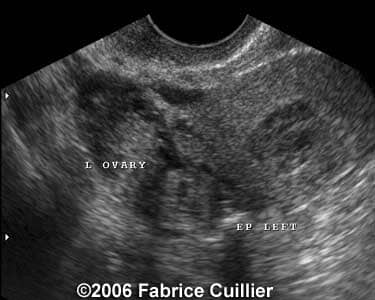

These are some cases of ectopic pregnancy (GEU) using the 2D and 3D scans.